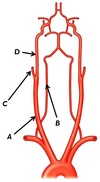

Name structures A, B and C

A - Fibula (right)

B - Tibia (right)

C - (interosseous membrane (right))